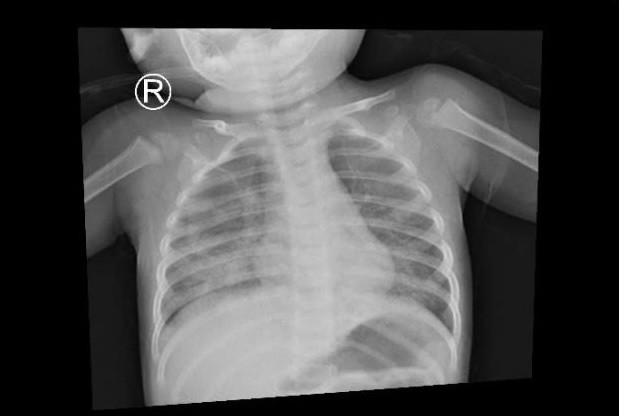

| Hình ảnh X quang ngực lúc nhập viện cho thấy, phổi của bé G.B. tổn thương. |